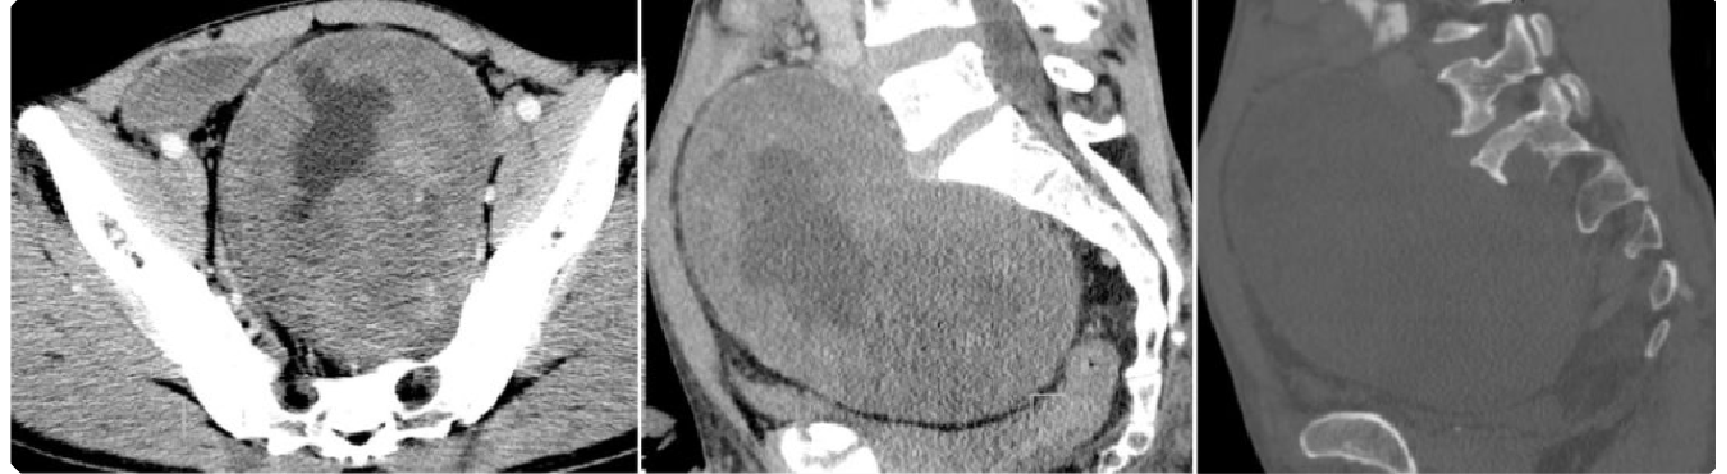

47df5e91be9763c0283a82cb0256446c.png 病例 23:(盆腔内)神经鞘瘤  46岁女性,因发现腹部肿块10余年,腹部隐痛1月余,实验室检查无特殊a1-a4为横断位多个层面;b1-b2为冠状位两个层面;c1-c2为矢状位两个层面;d为动脉和肿瘤的三维成像。肿瘤可见包膜,瘤体可见明显囊变坏死。免疫组化:S-100(+)、SOX-10(+)、CD117(-)、Dog-1(-)、 SMA(-)、Ki-67 (+,<1%)。特殊染色:PAS、网染无特殊。